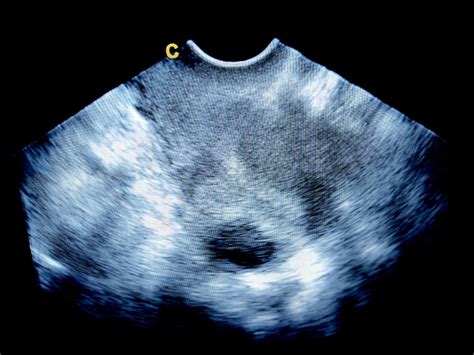

Morfologický ultrazvuk v 22. týždni

Morfologický ultrazvuk, nazývaný aj druhý veľký ultrazvuk, je detailné vyšetrenie anatómie plodu, ktoré sa zvyčajne realizuje medzi 18. až 22. týždňom tehotenstva. V 22. týždni je to ideálny čas na jeho absolvovanie. Toto vyšetrenie je kľúčové pre posúdenie zdravého vývoja dieťaťa a odhalenie prípadných vrodených vývojových chýb.

Je dôležité rozlišovať medzi morfologickým ultrazvukom a 3D/4D ultrazvukom. Morfologický ultrazvuk je predovšetkým diagnostické vyšetrenie zamerané na detailné posúdenie anatómie plodu a odhalenie abnormalít. Používa sa predovšetkým 2D zobrazenie.